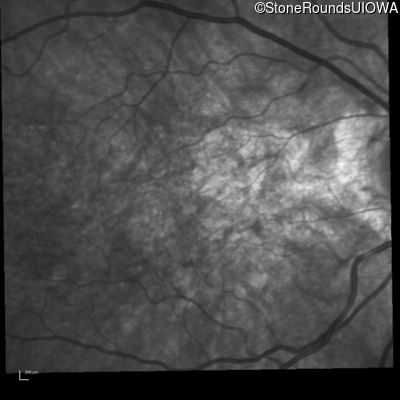

Infrared Fundus Photograph - Left - 20/30 -2 sc

Exemplar